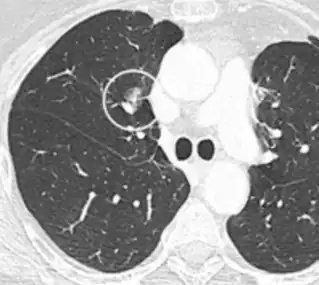

Lung nodule abutting a pulmonary cyst.[9]

• A lung nodule abutting a pulmonary cyst is a rare finding, yet indicating cancer.[9]